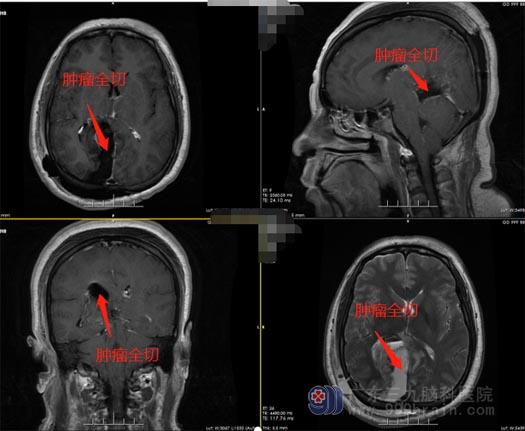

神经外五科专家团队查看后指出,患者病史明确,有手术指证,与家属详细介绍病情及手术方案及风险,决定予手术治疗。在排除手术禁忌症、完善术前准备后,神经外五科的医生团队在全麻下为李阿姨实施了“松果体区巨大脑膜瘤切除术”,术中肿瘤全部切除,电生理未见异常,麻醉满意,手术顺利。